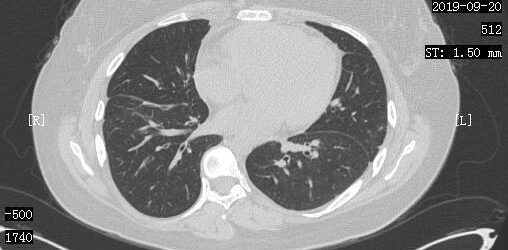

2019-4-12日CT:双肺病灶基本吸收

小周和她的家人非常高兴,同时也更加积极的配合医生进行治疗,加上小周平时也按时、适量的锻炼,逐渐的,小周发现自己的食欲也好起来了,抵抗力也增强了,到9月份再次复查的时候,我们发现小周的肺部情况非常好,同时全身骨转移灶也减少了。

2019-9-20日CT